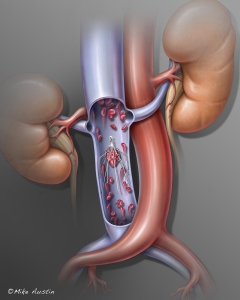

Welcome to my Patient and Professional Marketing page, where I harness the power of anatomical illustrations to educate and empower both patients and medical professionals. My unique approach combines artistry and education to convey complex surgical procedures and the utilization of medical devices in an easily understandable manner.